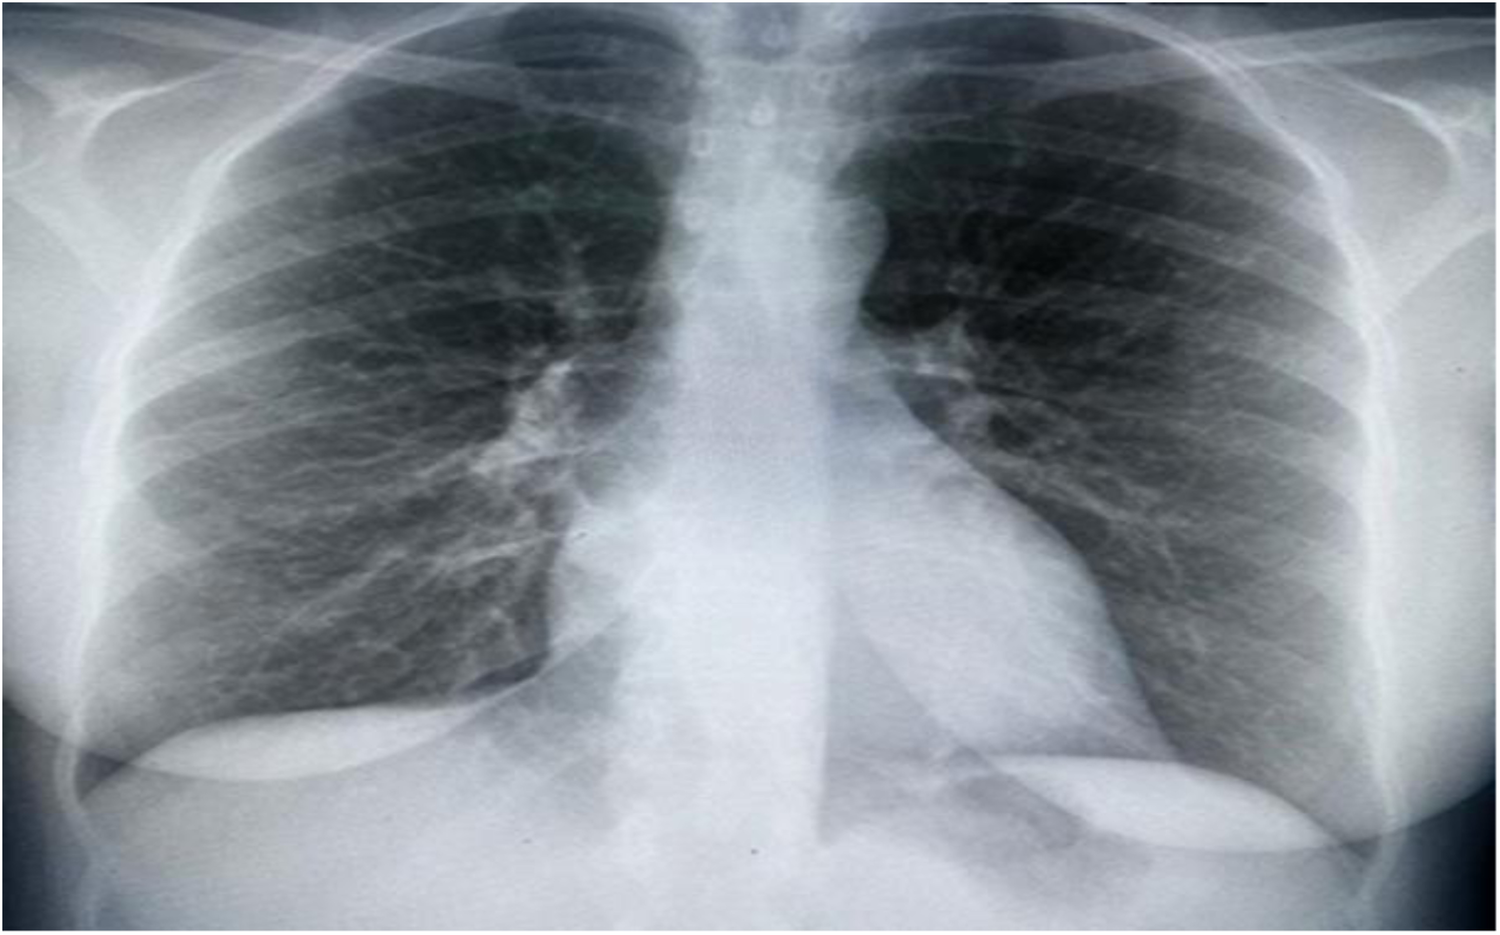

Upon assessment, the patient was in a semi-sitting position and slightly pale. Her pulse 110/min, blood pressure was 105/70 mmHg, and Spo2 was 95% on room air. Cardiovascular examination showed tachycardia, normal S1 and S2, no murmur, and no added sounds. Chest examination revealed symmetrical air entry with bilateral fine basal crepitation. Abdominal examination results were normal, with no organomegaly. Musculoskeletal examination was unremarkable, apart from bilateral lower limb edema. Neurological examination revealed sensory loss in the right dorsal foot and the left thumb. Electrocardiography (ECG) showed sinus tachycardia, no ischemic changes, or other abnormalities. Chest radiography revealed pulmonary congestion (Figure 1).

Figure 1

Chest x-ray showing bilateral interstitial opacities consistence with pulmonary congestion.